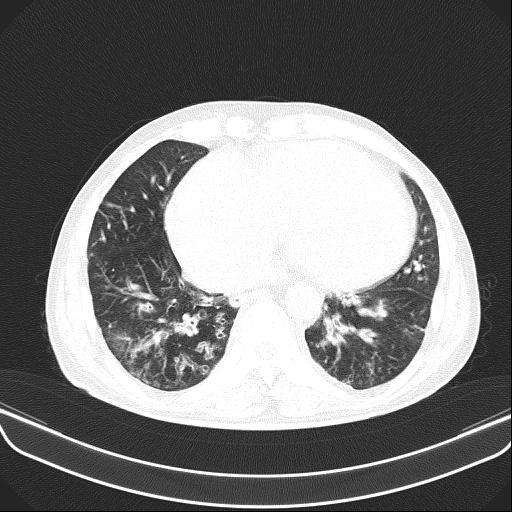

6月11日,会昌县人民医院呼吸内科接诊一呼吸衰竭的患者胡某,男性,54岁,主诉反复咳嗽、咳痰、气促10余年加重伴下肢浮肿10天入院。呼吸内科医生对胡某进行仔细查体:患者口唇及颜面、四肢紫绀明显,颈静脉怒张,桶状胸,肋间隙增宽,叩诊过清音,双肺呼吸音减弱,可闻及较多干湿性啰音,腹膨隆,肠鸣音减弱,双下肢重度浮肿。结合各类辅助检查,确诊胡某为“慢性阻塞性肺疾病、慢性呼吸衰竭、慢性肺源性心脏病失代偿期、重度肺动脉高压”。

不吸氧情况下胡某SPO2:67%,吸氧3L/min情况下SPO2:82%,治疗难度大,如何纠正严重的呼吸衰竭是重点。胡某重度浮肿、尿量少、腹胀明显、进食少,病情危重,随时有可能出现昏迷。同时,胡某神志清楚,无法配合无创双水平呼吸机辅助通气,不纠正呼吸衰竭,抗感染、祛痰、平喘、强心、利尿、扩血管等常规治疗几乎无效。

按照常规,医生会建议患者转ICU气管插管接有创呼吸机辅助通气或者转上级医院救治,但胡某拒绝转ICU,拒绝转上级医院,不接受气管插管及面罩式无创呼吸机辅助通气。经科内医生组讨论后决定:为避免患者气管插管或切开,使用经鼻高流量氧疗治疗,同时配合抗感染,雾化解痉祛痰,甲泼尼龙、多索茶碱平喘,托拉塞米、螺内酯利尿等治疗。经过13天时间治疗,胡某症状缓解、浮肿消退,好转出院。